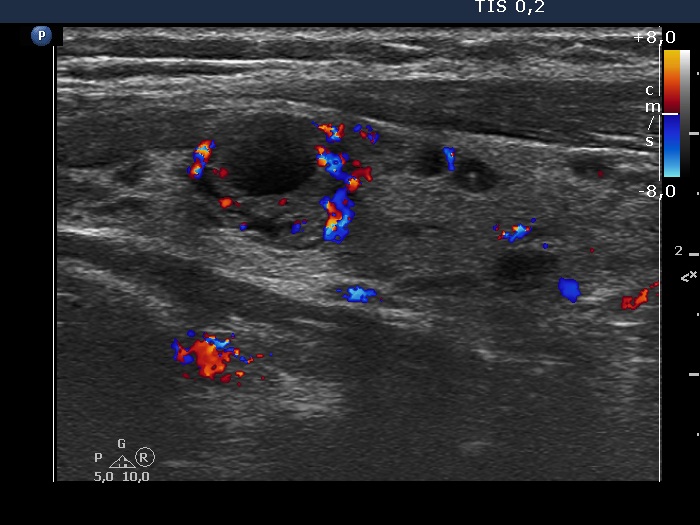

Study on 100 consecutive patients with thyroid nodule - case 054 (ultrasonographic picture 7)

Left lobe, longitudinal scan, color Doppler mode. The largest lesion presents intralesional blood flow.